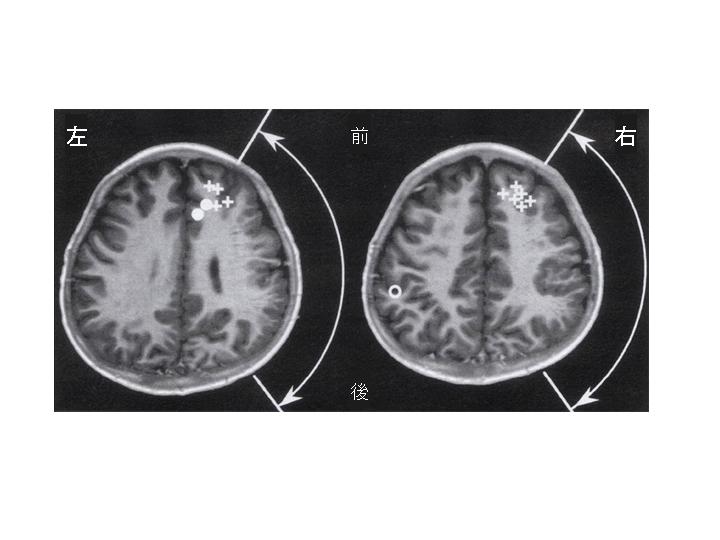

〈写真説明〉脳磁図の1例=広範な大脳皮質異形性(矢印の範囲)により、てんかんを繰り返す5歳児のケース=軽い右手の脱力があるが、感覚障害は無い。MEGにより、てんかん発作波は右前頭葉に推定された(+)。感覚刺激により左感覚野(○)は正常な位置(頭頂葉)に推定されたが、右感覚野(●)は前頭葉に移動していた。これは、脳が傷害を受けると新しい場所に機能が移る(可塑性)ことを、MEGは示している。